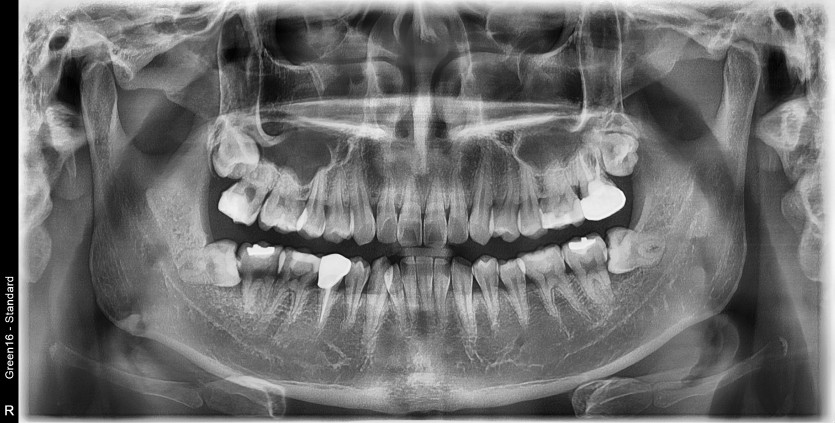

#38,48 사랑니 발치

구강 외과 전문의가 당일 발치했습니다.